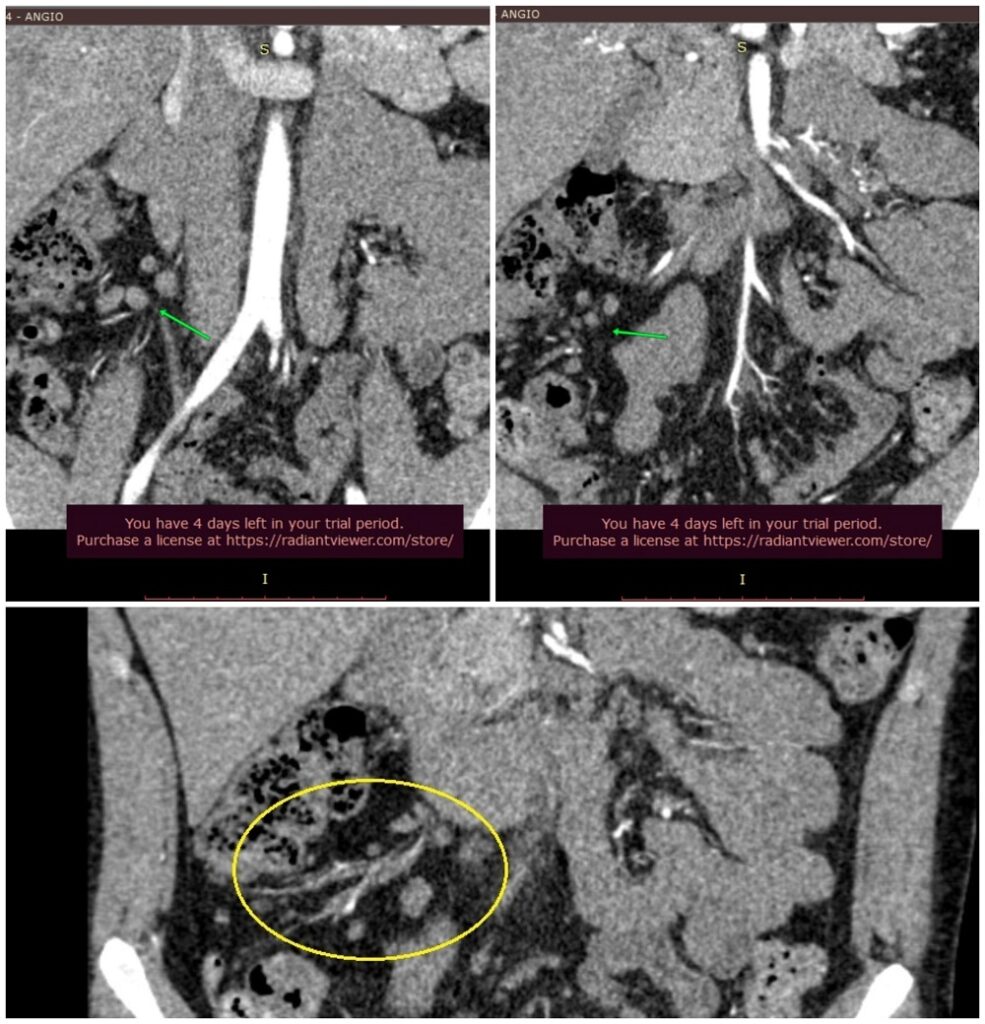

A 6. hónapban készült CT Angiográfia több mint egy tucat megnagyobbodott hasi nyirokcsomót (mesenterialis lymphadenomegalia) ábrázolt, amelyek mind számukban mind méretükben (15x12mm; 13x13mm; 11x5mm...) progressziót mutattak a 3. hónapban elvégzett has-kismedence CT-vel összehasonlítva. Ahol egyébként elbagatellizálták a nyirokcsomók méretét, számát, mondta el nekünk a CT Angiot leletező radiológus. Viszont hiába az eredmények , nem vettek mintát a temérdek nyirokcsomó egyikéből sem és nem foglalkoztak a leírt ritka hasi kórképpel, a duodenumot (nyombelet) összenyomó aortával és artériával, vagyis az Artéria Mesenterica Superior Szindrómával, ami ismert még Wilkie-szindróma néven is - és itt pecsételődött meg végleg a fiam sorsa.

Mivel ez a bejegyzés a Bartonella fertőzés oki lehetőségéről szól, itt nem írnék bővebben a fiam AMS-szindróma történetéről, ezt majd egy másikban megtesszük. Viszont AMS-szindrómát vizsgáló CT-n talált eltérések másik fele éppen a Bartonellózis egyik vezető tünete: a nyirokcsomó-megnagyobbodás. Ami a fiam hasi CT és MR felvételeit illeti, nem egy-két nyirokcsomója volt, hanem rengeteg - ezt a saját szemünkkel láttuk és onnantól fogva tudjuk, mióta 7 évvel később, 2022-ben Máthé Zoltán Professzor Úr (Semmelweis Egyetem Transzplantációs Klinika korábbi igazgatója) megmutatta nekünk a felvételeket és segítsége után a fiam sok órát, napot beletéve megtanulta értelmezni felvételeit a Radiant segítségével a kapott diagnózisai, vagyis a nyirokcsomók, az AMS és a paraduodenalis (belső) sérv kapcsán.